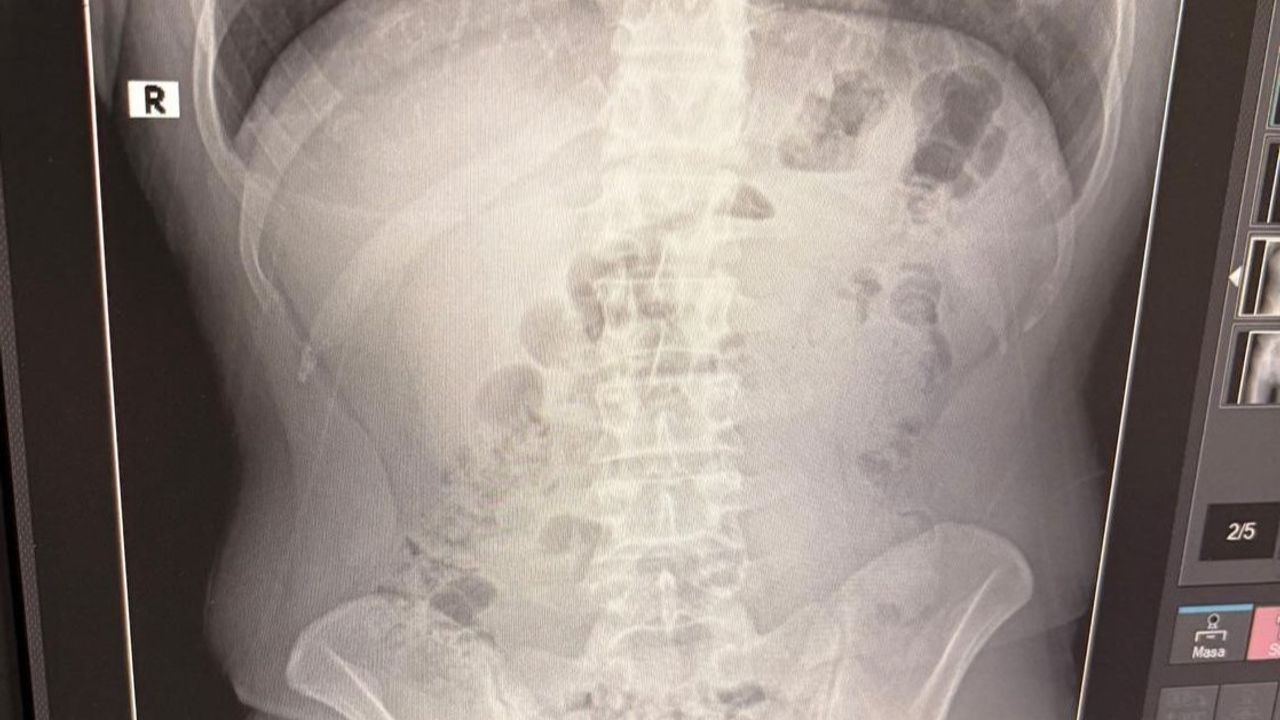

Adreste yapılan arama sırasında ekipler, şüphelilerden birinin üstünde 1 adet kapsül ele geçirdi. Şüphe üzerine tüm şüpheliler hastaneye götürüldü ve yapılan röntgen kontrollerinde 3 kişinin midelerinde kapsül içine gizlenmiş metamfetamin tespit edildi.

Hastanede tedavi altına alınan şüphelilerin vücudundan kapsüller çıkarılırken, adreste ele geçirilenlerle birlikte toplam 1 kilo 516 gram metamfetamin ele geçirildi.